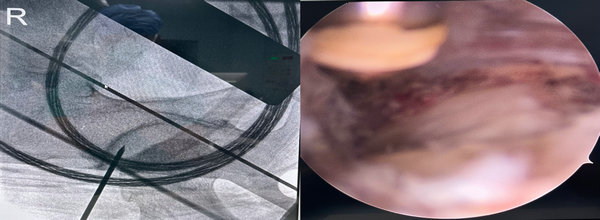

定位影像及镜下表现

骨外科一病区开展保髋治疗术中